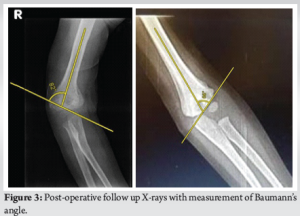

Patient who underwent surgery received pin tract dressing weekly or biweekly. K-wires were removed 4–6 weeks after surgery once an X-ray confirmed with adequate callus formation. Simultaneously, the POP splint was removed, and the patients were encouraged for elbow range of movement. Follow-ups were at 6 weeks, 3 months, and 6 months after surgery. The patients were assessed with Mayo elbow score and Baumanns angle (Table 1).

A total of 35 pediatric patients, aged between 2 and 12 years (mean age: 7.15 years), underwent supracondylar pinning for the supracondylar humerus fractures. Of these, 22 were male and 13 were female. In the study, 21 cases involved the left side, while 14 cases affected the right side. Extension-type fractures were observed in 93% of patients, while 7% had flexion-type fractures. All patients were followed up for a minimum of 6 months. Superficial pin tract infections developed in 10 patients, all of whom recovered after pin removal and oral antibiotics treatment. No cases of severe infection or septic arthritis were reported. Cubitus rectus seen in 3 patients (8%) who showed positive functional outcomes during the follow-up. No instances of neurovascular injury, compartment syndrome, and migration of the pin were observed in this study. At the 6-month follow-up, the mean Mayo Elbow score was 96.01 ± 2.80. Based on this assessment, 31 patients achieved excellent outcomes, while 3 had good outcomes and 1 had fair outcome. No poor outcomes were recorded. The mean Baumanns angle was 75.90 ± 10.01 (Fig. 1-4].

Supracondylar humerus fractures are one of the most common fractures that affect children. It constitutes for more than 50% of elbow fractures. The fractures typically occur within the first 10 years of life and affect the distal humerus, near the metaphysis. It is of two types – flexion and extension type [6]. The standard treatment involves closed reduction followed by percutaneous pin fixation. Several treatment methods have been used in the management of supracondylar humerus fractures. Non-surgical treatment is generally considered only for fractures that are not displaced or displaced minimally. They are managed with reduction and stabilized with a POP cast. However, in cases of displaced or open fractures, surgical intervention is necessary to prevent complications, such as malunion, cubitus varus, restricted elbow movement, and persistent pain. Open reduction with fixation is recommended in specific scenarios, such as open fractures requiring vascular exploration or fractures that cannot be reduced by closed methods. In this study, the average age of the children was 7.15 years, ranging from 2 to 12 years. A study conducted in Saudi Arabia by Khan et al. reported a similar mean age of 8.1 years [7]. The majority of our study population was between 5 and 10 years (62%), which is consistent with the findings by Fowels et al. According to Reising et al., supracondylar humerus fractures were common for the ages above 4 years and below 9 years [8]. This study also found that boys were more frequently affected than girls (62.8% vs. 37.2%), a trend that aligns with findings by Devkota et al., who reported male–to-female ratio of 58:44. This difference is due to boys higher level of sports and physical exertion, making them more susceptible to falls and injuries [9]. Among 35 cases, 21 involved the left arm while 14 affected the right side. These findings correspond with those of Devkota et al., who reported a left-to-right arm ratio of 54:48. This pattern is often attributed to the protective function of the non-dominant limb during falls [9]. The clinical outcomes in this study were assessed using the Mayo Elbow score. At the 6 month follow-up, the mean score was 96.01 ± 2.80, which aligns with findings by Sinikumpu et al., who reported a mean score of 96.4 in patients with modified Gartlands type 3 fractures [10]. Similarly, Ulmar et al. documented excellent outcomes, reinforcing the effectiveness of the treatment approach used in this study [11]. On an anteroposterior radiograph, Baumanns angle is defined as the angle formed between the physeal line of the lateral condyle and the distal humeral metaphysis in relation to the long axis of the humerus. At 6 months, three patients showed cubitus rectus. The standard Baumanns angle ranges from 64° to 81°. In this study, the mean Baumanns angle at 6 months was 75.90 ± 10.01, which is within the acceptable range. Similar results were observed in a study by Lee et al., which found no significant changes [12]. In addition, Kitta et al. had used humeral capitellar angle to assess how the fracture fragments were reduced, and specifying the importance of maintaining the carrying angle. The mean humeral capitellar angle was 72.3 [13]. Basaran et al. conducted a similar study, reporting an insignificant difference between closed reduction with or without a medial incision [14].